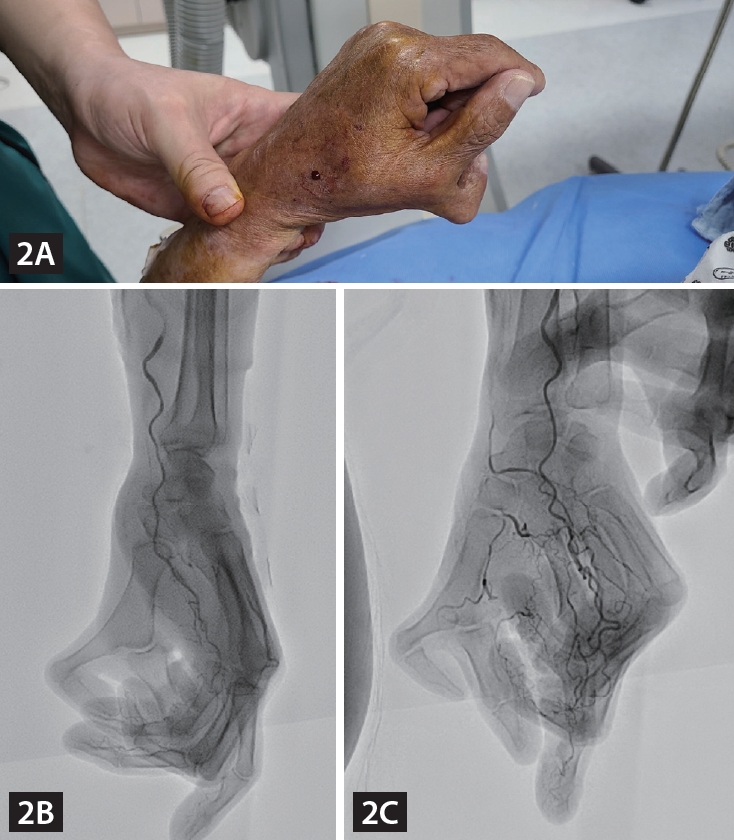

An 82-year-old male patient was admitted due to atypical chest pain, and he underwent coronary angiography (CAG) via a left distal radial access (DRA). We found that he had polydactyly of his left hand, which could be classified as Wassel Type 4 polydactyly (Fig. 1) [1]. We were concerned about the anatomical variation of the left distal radial artery due to the anomaly, but a distal radial pulsation was easily palpated in the anatomical snuff box, and a successful puncture was performed. A CAG was performed using a 5 Fr vascular access sheath 10 cm in length, according to the usual method, and it revealed mild narrowing (Supplementary Video 1-3). We wanted to determine the intact natural vascular anatomy of the polydactyly-affected hand; hence, we performed manual compression for 10 minutes after sheath removal and performed brachial angiography via brachial puncture with a 20G angiocath cannula. Angiography showed the usual run-off of the left distal radial artery through the anatomical snuff box, and there was an additional digital branch to the accessory thumb (Fig. 2, Supplementary Video 4). The puncture site was compressed for an additional two hours with a gauze block and simple elastic bandage to ensure complete hemostasis.